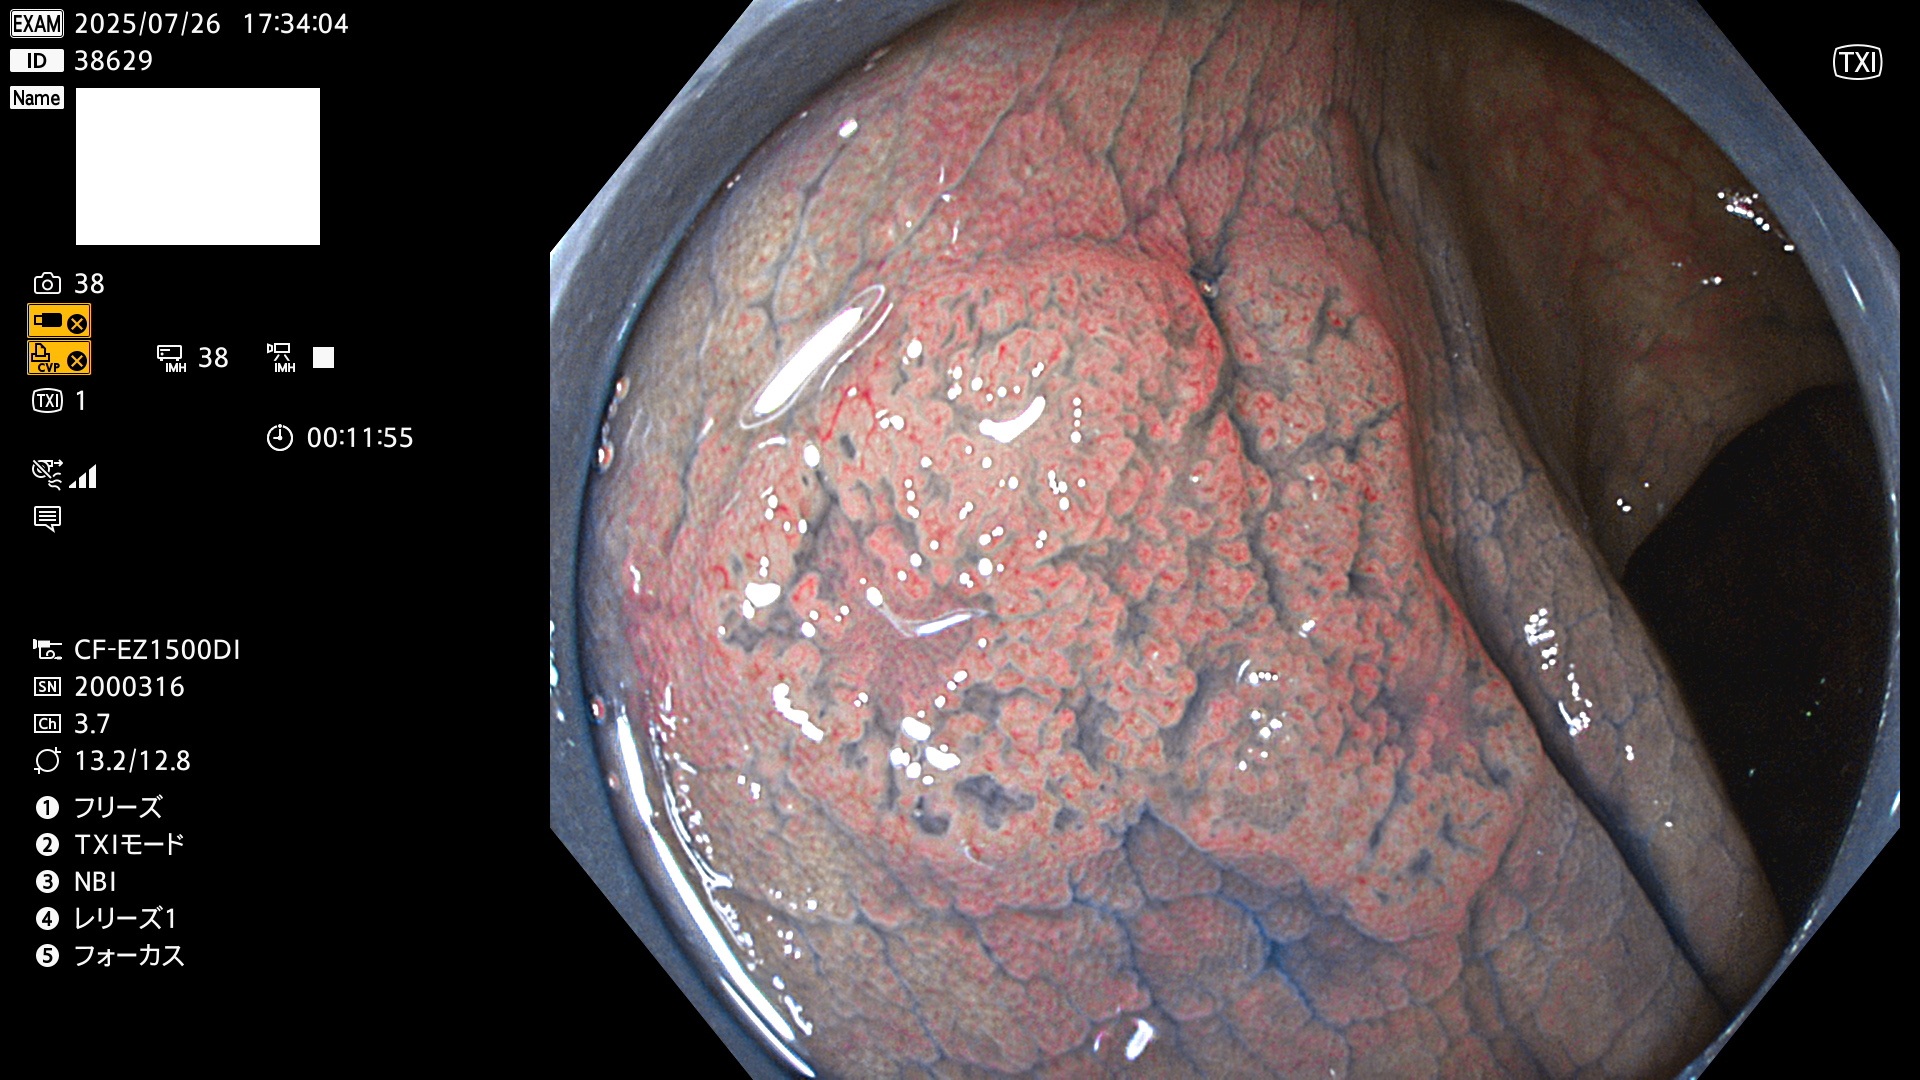

完全に平坦な物をUb、陥凹している物をUcと呼びます。Ubは認識が困難で、Ucはびらん(炎症)と紛らわしいために見落とされやすく、「内視鏡後・大腸癌」の原因になります。

専門的)Uc=De Novo癌? 内視鏡の解像度が低かった時代、このような説もありました。しかし今日の高精度内視鏡では良性の微小なUc型腺腫(APC遺伝子異常の腺腫)が日常的に見つかります。Ucこそが多段階発癌(Adenoma-Carcinoma Sequence)のMain Routeです。

専門的)細胞生物学的Ucの再定義UcをPitと形態学で定義するのは医学的には全く不毛です。Ucの本質はIntraTumor HeterogenityとTumor Dormancyが微小病変に見られる点です。これは早い腫瘍進化=ゲノム不安定性を意味します。そのような病変は隆起型でも形態によらずUcと定義すべきです。なぜなら1年後には陥凹し典型的Uc(最悪の場合NPG癌)になるからです。

2025年7月24日〜7月27日の4日間(40件)15個 (Uc_ADR=15個/40人=38%)